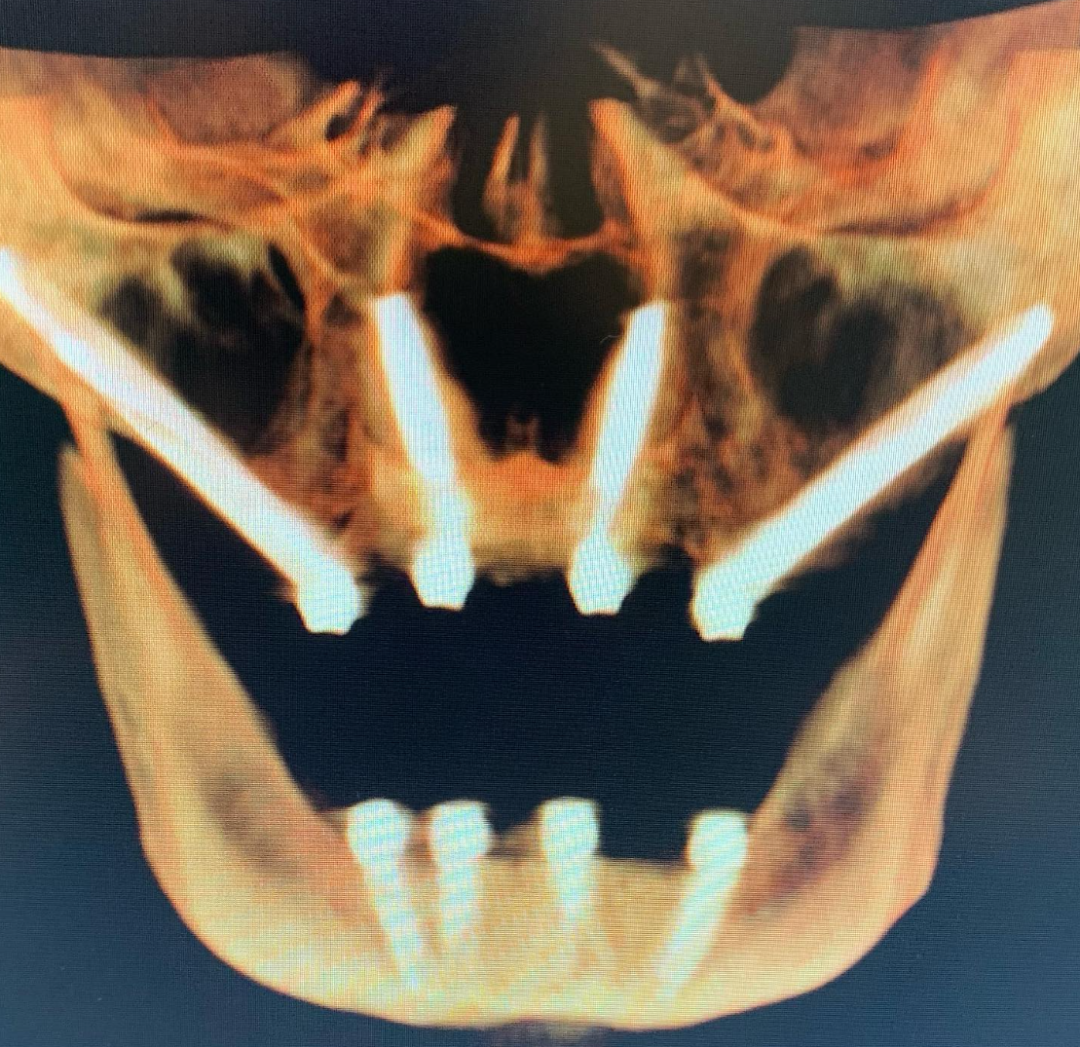

经鼻种植体必须由精通远程锚定种植技术(且具备丰富临床经验)的种植专科医师实施。该技术能在确保安全的前提下实现即刻负重。若不符合经鼻种植条件,患者只能选择上颌四联颧骨种植或通过块状骨移植重建前牙区骨量。

需特别说明的是,原作者在鼻底骨(梨状孔边缘)锚定种植体的临床实践已逾二十年。对于全牙弓修复的上颌前牙区种植,鼻基底骨植入始终是推荐方案——该部位能提供极高的扭矩稳定性,显著减少种植体微动,结合面部扫描与口内扫描(IOS)/摄影测量技术,可实现安全可靠的即刻负重。

长期预后评估:相较于四联颧骨种植,经鼻种植体可能具有更优的长期效果。结合翼突种植可完全消除悬臂梁效应,其宽间距植入布局也更具生物力学优势。